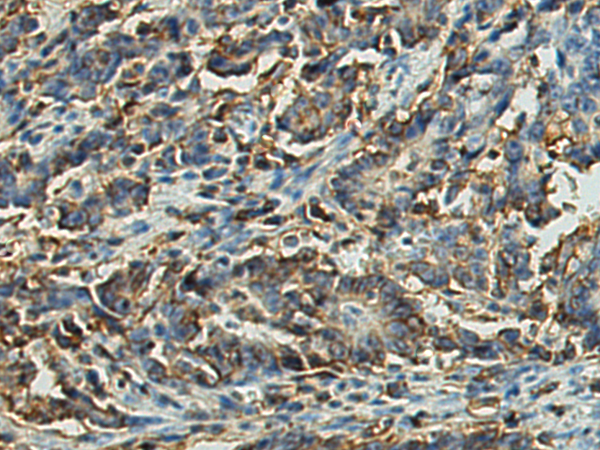

IHC positive control:

Human gastric cancer and Human ovarian cancer

IHC Recommend dilution:

50-100